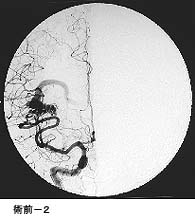

(2)脳動静脈奇形に対する液体塞栓物質を用いた治療

*治療により異常血管は閉塞されました。